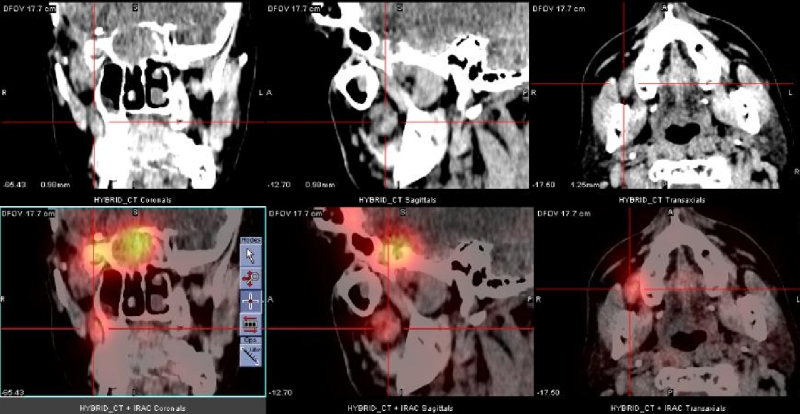

Uma quarta recorrência foi identificada por RM na região retro-orbital direita com progressão ipsilateral anterior para lobo temporal após cinco anos. Investigação pré-operatória constatou uma massa pulmonar na parte inferior do lobo superior esquerdo. Biópsia guiada por CT evidenciou meningioma atípico grau II. Um estudo com 111In-Oct SPECT/CT foi realizado como extensão diagnóstica. Foi evidenciada intensa fixação do 111In-Oct associada à presença de receptores de somatostatina a nível da lesão pulmonar (fig. 1), assim como na lesão temporal direita (fig. 2), confirmando recorrência. Tambén foi detectada fixação linfonodal direita (fig. 3).